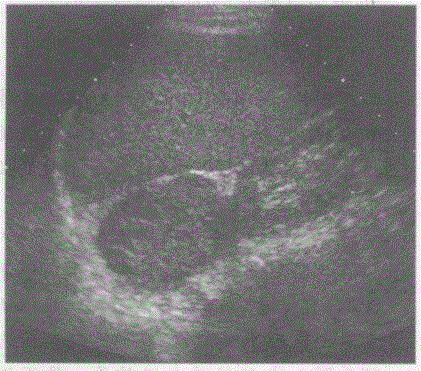

问题 临床资料:女,38岁,自诉反复发作性心悸、气短,恶心、呕吐,持续性血压升高,发作时加重3年余,服用降压药血压控制不理想。 超声综合描述:右侧肾上腺区可见4.1cm×3.5cm椭圆形低回声区,有完整增强回声包膜,内回声欠均匀,CDFI:其内及周边可见短线样血流信号,为低阻血流。见下图及彩图64。 {图1} {图2} 超声提示:

选项 A.肝右叶实性占位(肝癌) B.右肾上极实性占位(肾细胞癌) C.右肾上腺实性占位(嗜铬细胞瘤) D.右肾上腺囊性占位(囊肿)

答案 C